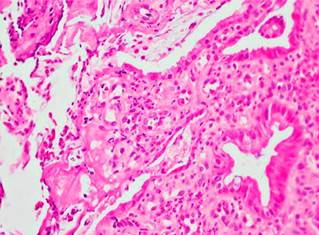

Ileocolonoscopy identified solitary rectal ulcer, with no lesions in the ileal mucosa. Histopathology samples from May 2016 were evaluated by institutional pathologists, in which mucosa with tissue artifacts was found with focal presence of cell groups with cytologic and architectural atypia (Figure 4), so adenocarcinoma was initially suspected based on the inflammatory reactive changes. However, the lesion was not represented in immunohistochemical sections. In the new samples obtained at our center, hyperplastic mucosa was found without dysplasia, as well as ulcer fragment without tumor lesions (Figure 5); no architectural changes, microorganisms, granulomas, or clear fibromuscular replacement of the lamina propria were observed.

Figure 4 Fibroinflammatory replacement of the lamina propria. Hematoxylin and eosin stain (H&E): 10 X.